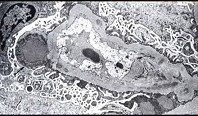

- 单项选择题阅读下面两张图片(电镜箭头示上皮下驼峰状电子致密物沉积)后,其病理诊断为 ( )

E、毛细血管内增生性肾小球肾炎